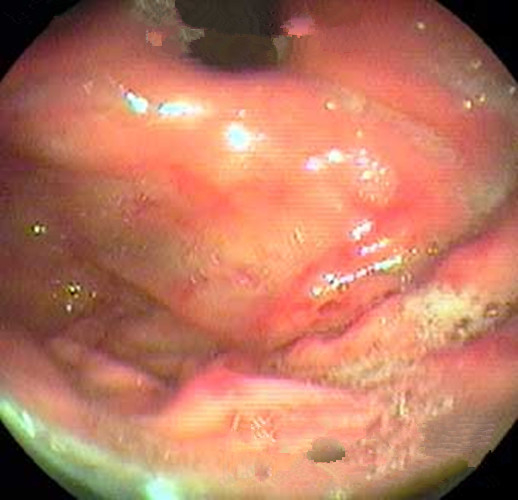

淺表型糜爛出血慢性胃炎